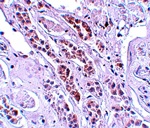

图片:

Immunohistochemistry of TCTN1 in human kidney tissue with TCTN1 antibody at 5 ug/mL.